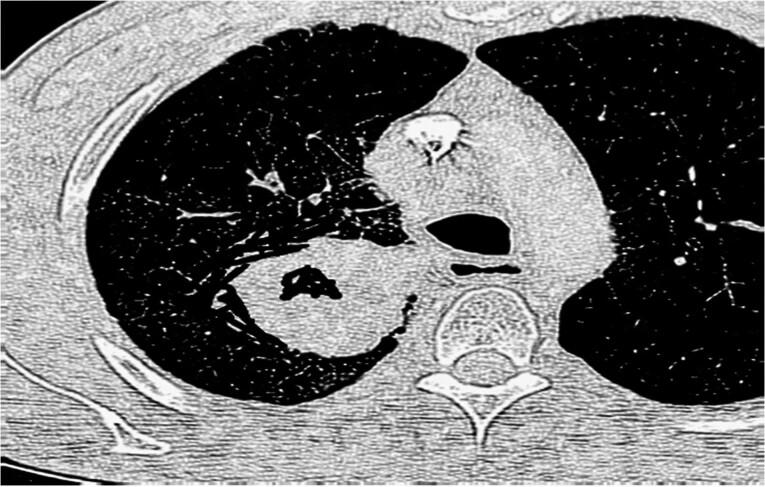

Hereby, we report the case of a 59-year-old male who was admitted with general weakness. The electrocardiography (ECG) changes revealed CHB, short QT interval due to short ST segment, and generalized ST elevation. The initial calcium level was 15.8 mg/dL (high), and serum levels of parathyroid hormone (PTH), vitamin D, and phosphorus were normal. A chest computed tomography scan showed a large, central mass with cavitation in the right lung. After an initial diagnosis of lung cancer and paraneoplastic hypercalcemia, the patient was treated with normal saline, calcitonin, and zoledronic acid, whose calcium levels decreased to 10.4 mg/dL after 4 days. Pathological ECG findings were also resolved after the correction of serum levels of calcium.

Hypercalcemia sometimes occurs as a paraneoplastic syndrome following the production of PTH-related peptide by malignant cells, including squamous cell carcinoma of the lung. Complete heart block associated with paraneoplastic syndrome has been reported so far in only one study.